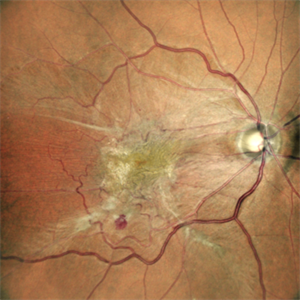

Choroidal Neovascular Membrane

Oct 14 2022 by Vaidehi Sathaye

Fundus photograph of LE of a 68 year male patient with a choroidal neovascular membrane

Photographer: Dr. Vaidehi Sathaye

Imaging device: Mirante

Condition/keywords: CNVM